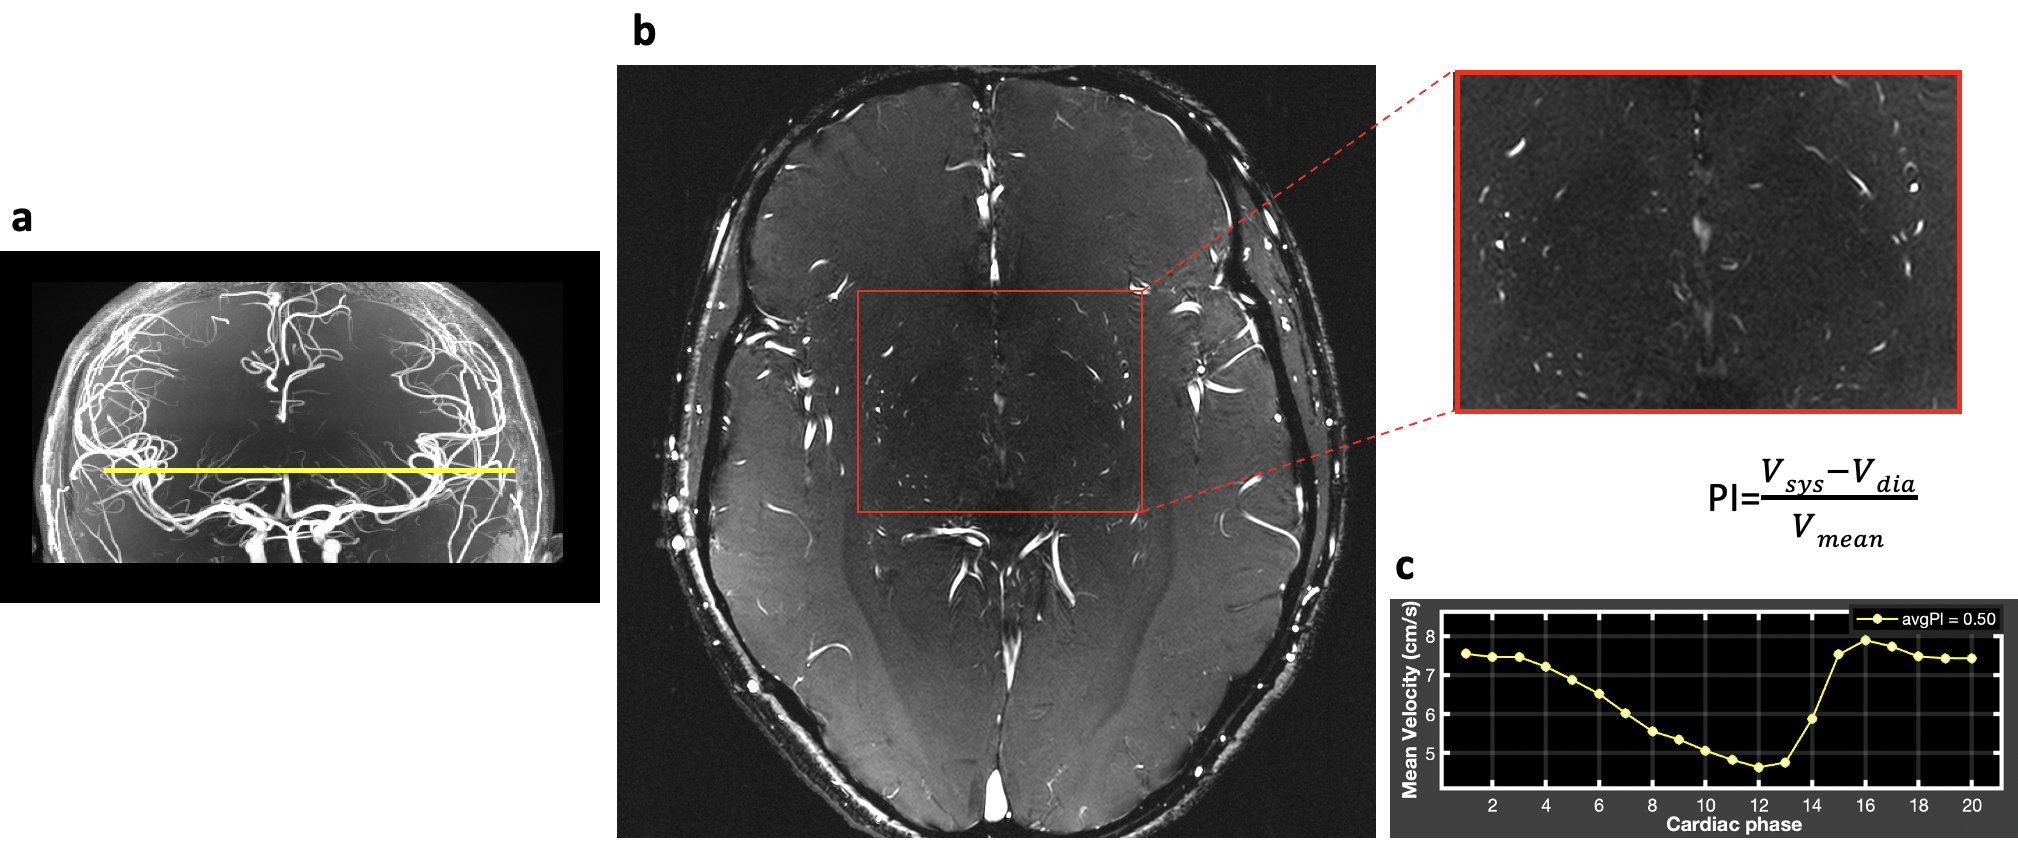

All experiments were performed on a 7T MAGNETOM Terra MRI system (Siemens Healthcare, Erlangen, Germany) using an 8-transmit/32-receive head coil (Nova Medical, Wilmington, MA). Retrospectively gated single-slice 2D PC-MRI sequences with VENCs of 20 cm/s and 40 cm/s were acquired on 31 participants (age: 51.8 ± 21.5). The other image parameters included: FOV = 180x200 mm2, slice thickness = 2 mm, voxel size = 0.2x0.2x2.0 mm, flip angle = 58°, TE/TR= 9.72/95ms, 20 phases across a cardiac cycle. A 3D high-resolution TOF was performed on each subject prior to PC-MRI scans to locate the perforating arteries (Figure 1a). Test-retest PC-MRI scans were performed on 8 participants to evaluate the reproducibility of PI measurement. PC-MRI scans with temporal resolutions of 63ms, 95ms, and 127ms were performed on 9 participants to test the effects of temporal resolution on the sensitivity of perforator detection and the reliability of PI measurement.

Figure 1. a. TOF image. Yellow line indicates the imaging position of PC-MRI. b. PC-MRI structural image. Red box indicates the basal ganglia region where the LSAs locate. c. The resulting velocity profile and PI calculation of LSAs.